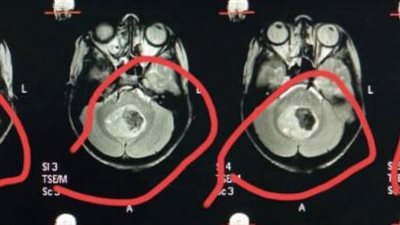

نجاح أول جراحة مخ وأعصاب بمستشفى تمى الأمديد بالدقهلية

فريق جراحي بمستشفى بلبيس ينقذ حياة طفلة أصيبت بكسر في الجمجمة ونزيف بالمخ

سوهاج الجامعى تنجح في استئصال "ورم خبيث" يزن 100 جرام بالمخ